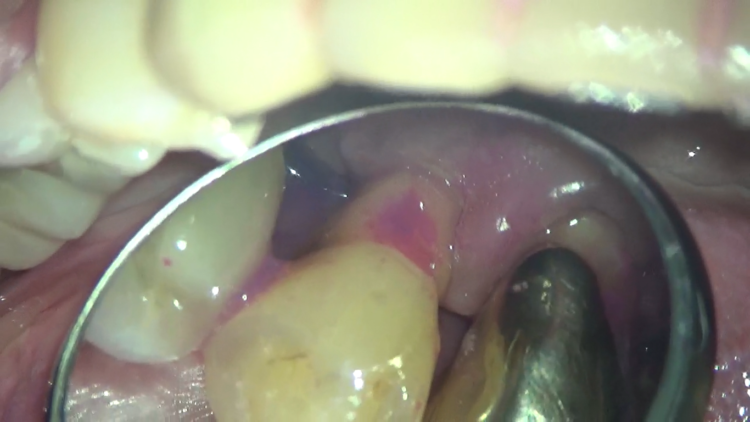

これは、左下の裏側です。プラークの染め出しを行ってみると、ベッタリと紫色に染まっています。

裏側なんて、考えただけでも磨きにくそうですね・・・。

表側から通しただけなのに、ここまできれいになりました!!